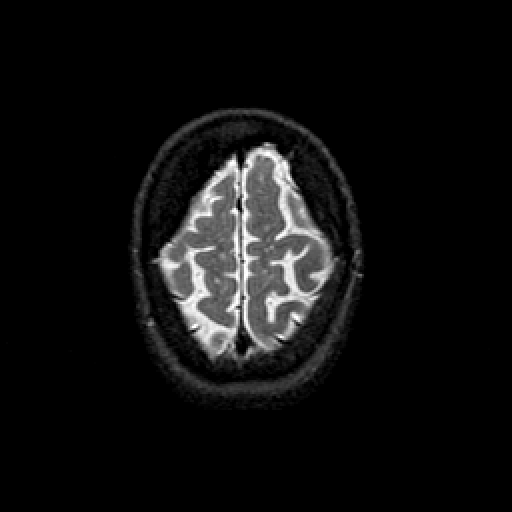

T2-weighted structural MR: Slice 46

Slice 46